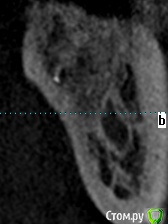

meld Опубликовано 7 ноября, 2017 Автор Поделиться Опубликовано 7 ноября, 2017 Прицельный снимок 38 зуба и его срезы Ссылка на комментарий